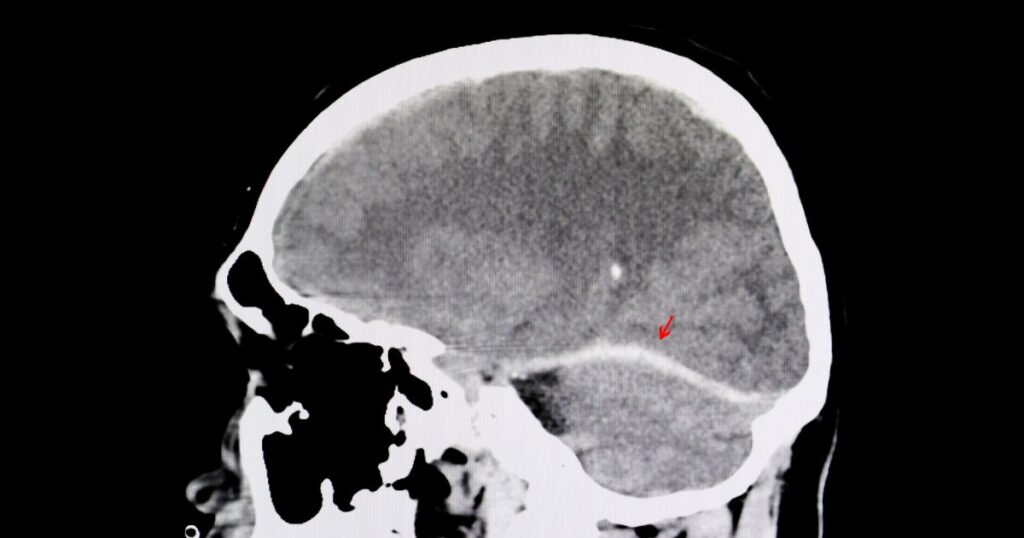

Semi-truck and corporate negligence caused traumatic brain injury. Our client suffered a traumatic brain injury as a result of the defendant’s negligence in parking a commercial vehicle. The key to this case was understanding trucking regulations and local ordinances at play to show how the situation should have been handled safely.